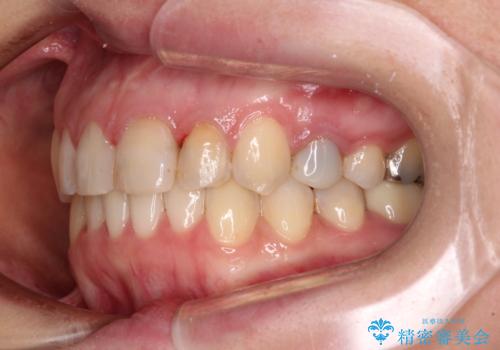

【モニター】前歯のデコボコと奥歯の虫歯 インビザライン治療と奥歯のセラミック治療

- 前歯のデコボコと奥歯の虫歯を気にして来院された患者様です。

主に下顎歯列全体の後方移動とIPR(歯と歯の間を削る)によってデコボコが解消するように設計し、インビザラインにより治療を行うこととしました。

矯正治療後半に下顎左右奥歯をセラミッククラウンにて補綴し、その後インビザラインによる歯列の仕上げを行うこととしました。

下顎前歯の叢生が速やかに改善されたため、1年3か月で治療を終えることができました。

下顎前歯は後戻りを起こしやすいため、舌側を細いワイヤーで固定することで後戻り対策を行っています。